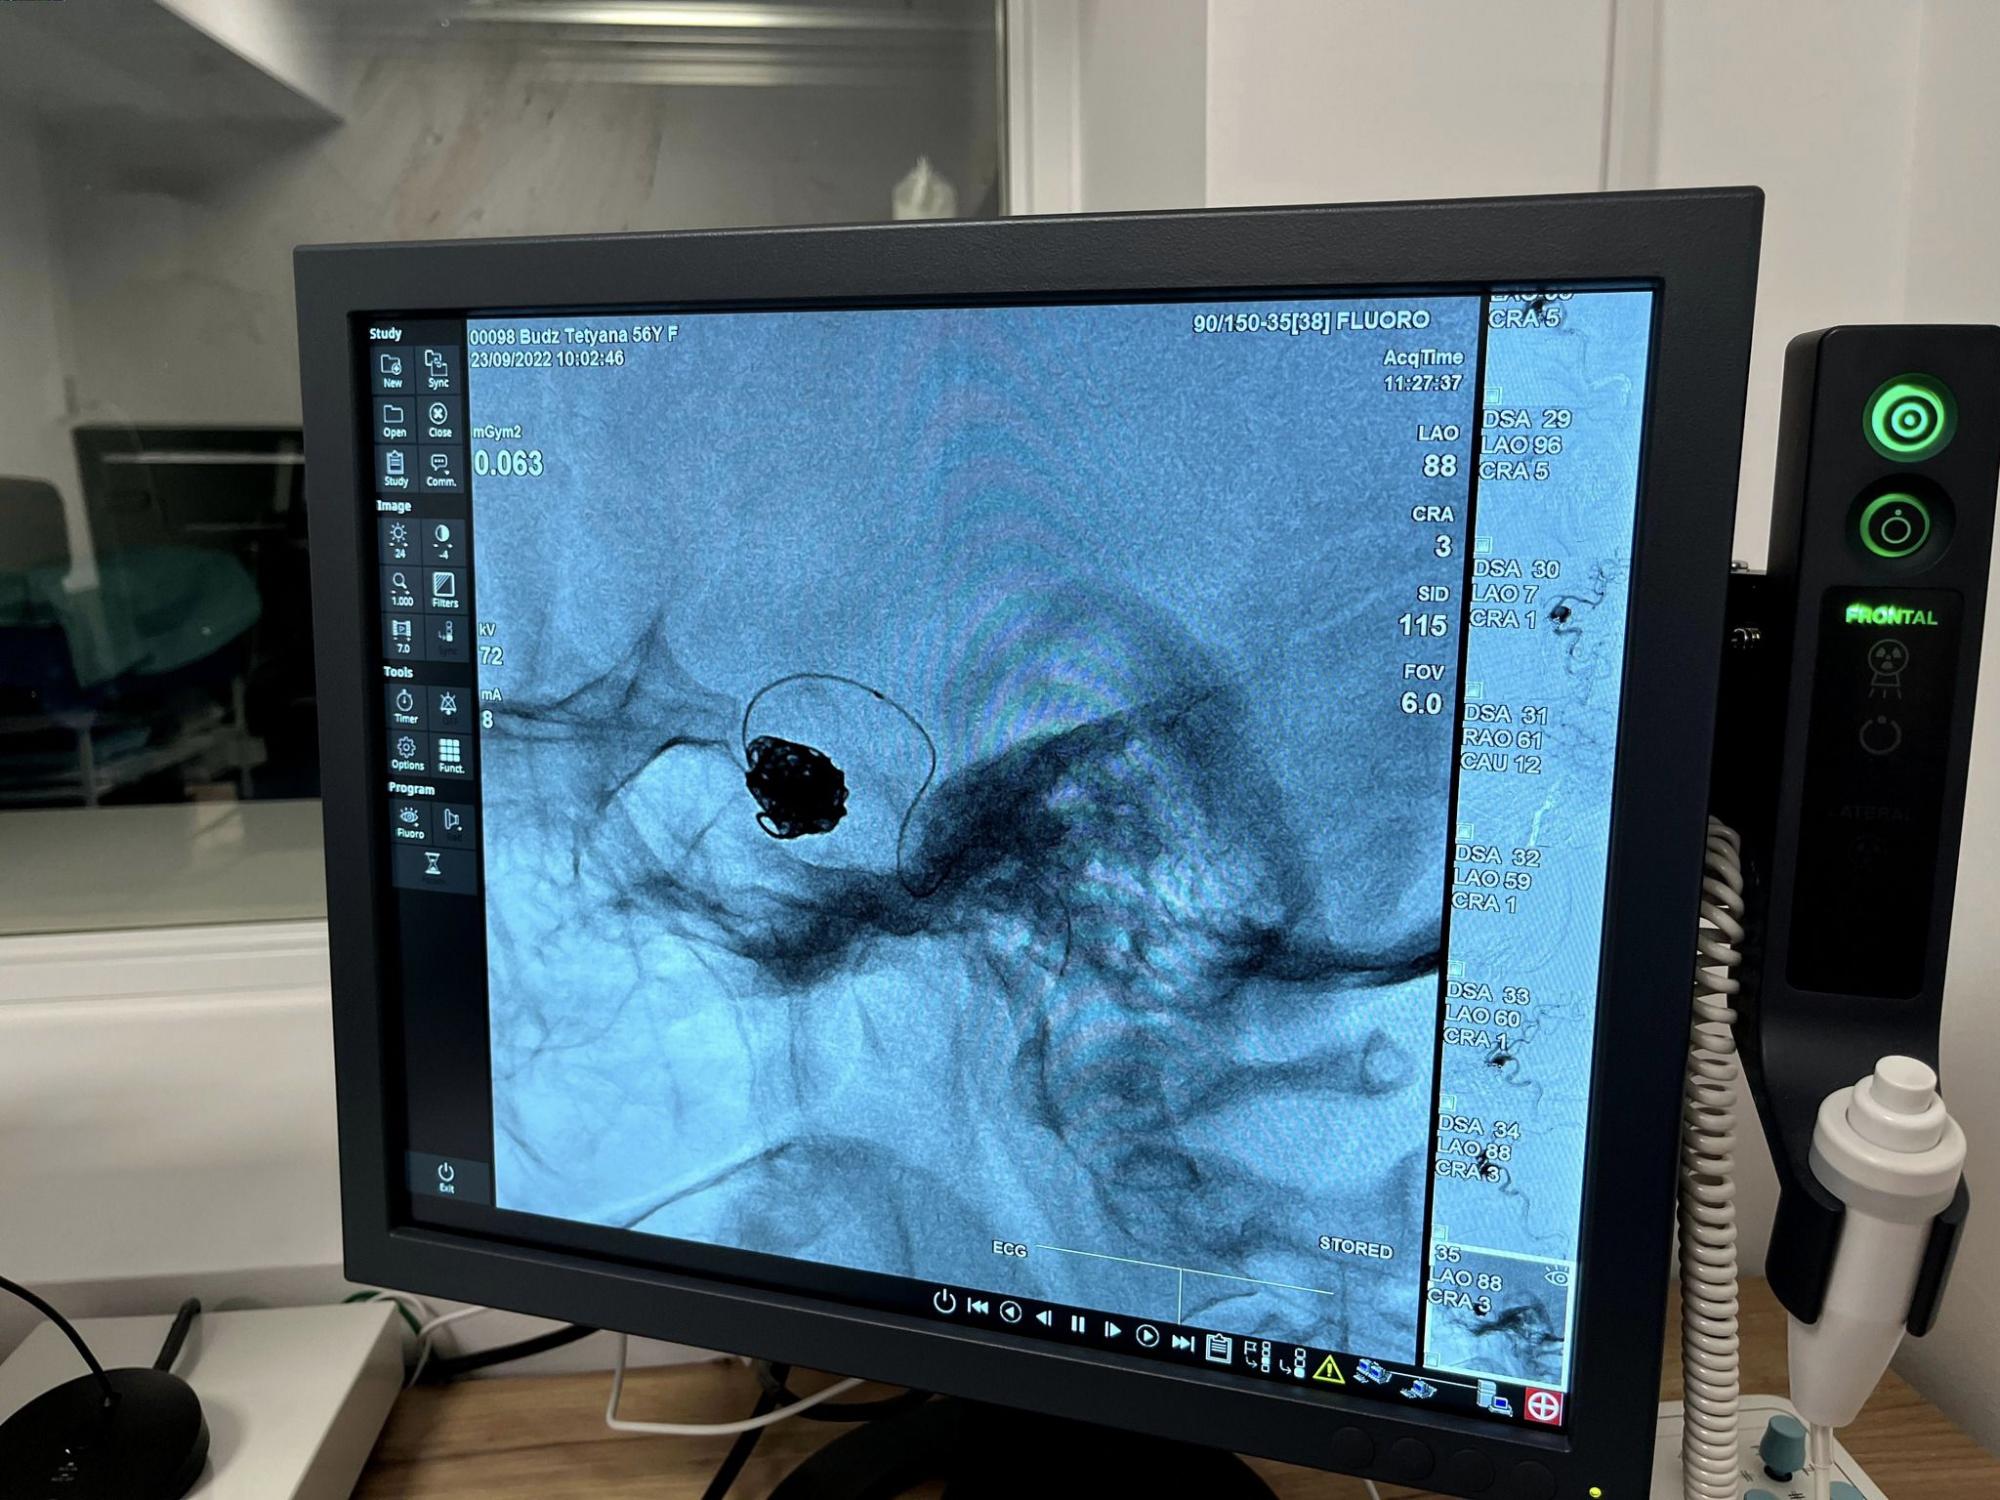

Специалисты больницы Святого Луки Первого медицинского объединения Львова спасли жизнь 56-летней пациентки, которую госпитализировали с огромной аневризмой головного мозга размером в полтора сантиметра.

По их словам, после диагностики женщине сообщили, что у нее большая аневризма мозговой артерии. И уже на следующий день специалисты отделения реперфузионной терапии и радиологии выполнили эмболизацию - закрытие аневризмы с помощью мозговых спиралей.

Отмечается, что операция прошла без разрезов - только одним проколом длиной до 5 мм.